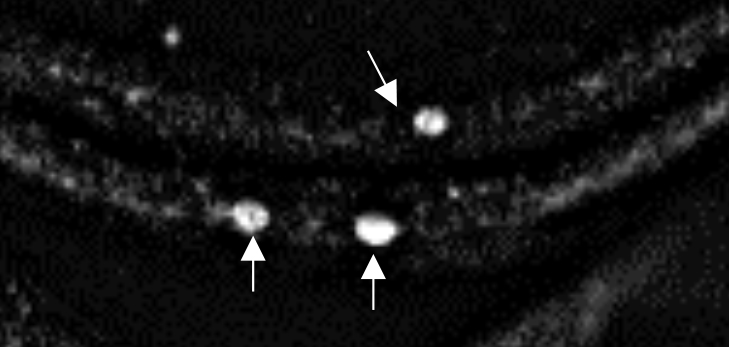

An epifluorescence microscope image shows clumps of human alpha-synuclein aggregating in the neurons of a fruit fly larva. Credit: Anderson, Hirpa, Zheng, Banerjee and Gunawardena, Frontiers in Cellular Neuroscience, Jan. 2020. The image is cropped from a graphic published in the journal article, which is distributed under Creative Commons Attribution License CC BY 4.0 (https://creativecommons.org/licenses/by/4.0/).

Alpha-synuclein is known to form abnormal clumps in the brains of patients with Parkinson’s, but scientists are still trying to understand how and why this happens.

The new study explores alpha-synuclein’s basic properties, with a focus on a section of the protein known as the non-amyloidal component (NAC). The research was done on fruit fly larvae that were genetically engineered to produce both normal and mutated forms of human alpha-synuclein.